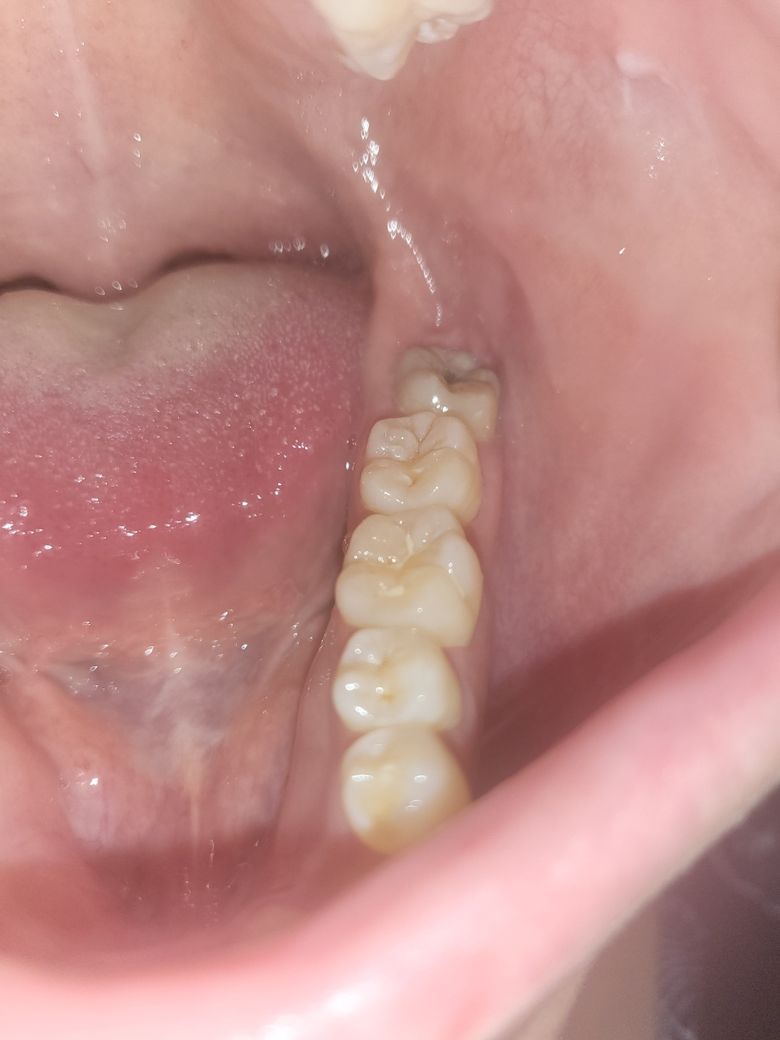

사랑니 발치 질문합니다. 엑스레이 사진 첨부해서요 ?

교정을 위해 사랑니를 뺴려고 합니다... 찾아보니 사랑니는 잇몸을 쨰고 뺴면 마취 풀린후 통증이 매우 심하다고 다들 그러네요..

저는 잇몸을쨰고 빼야하는지 궁금합니다. 나이는 25살 남자입니다.

이미 사랑니가 나와 있는 상황에서는 잇몸을 절개하지 않고 발치가 가능합니다.

잇몸을 절개 하지 않고 발치를 해되 될것같습니다. 크게 통증이 잇을 사랑니는 아니니 너무 걱정하지마세요.